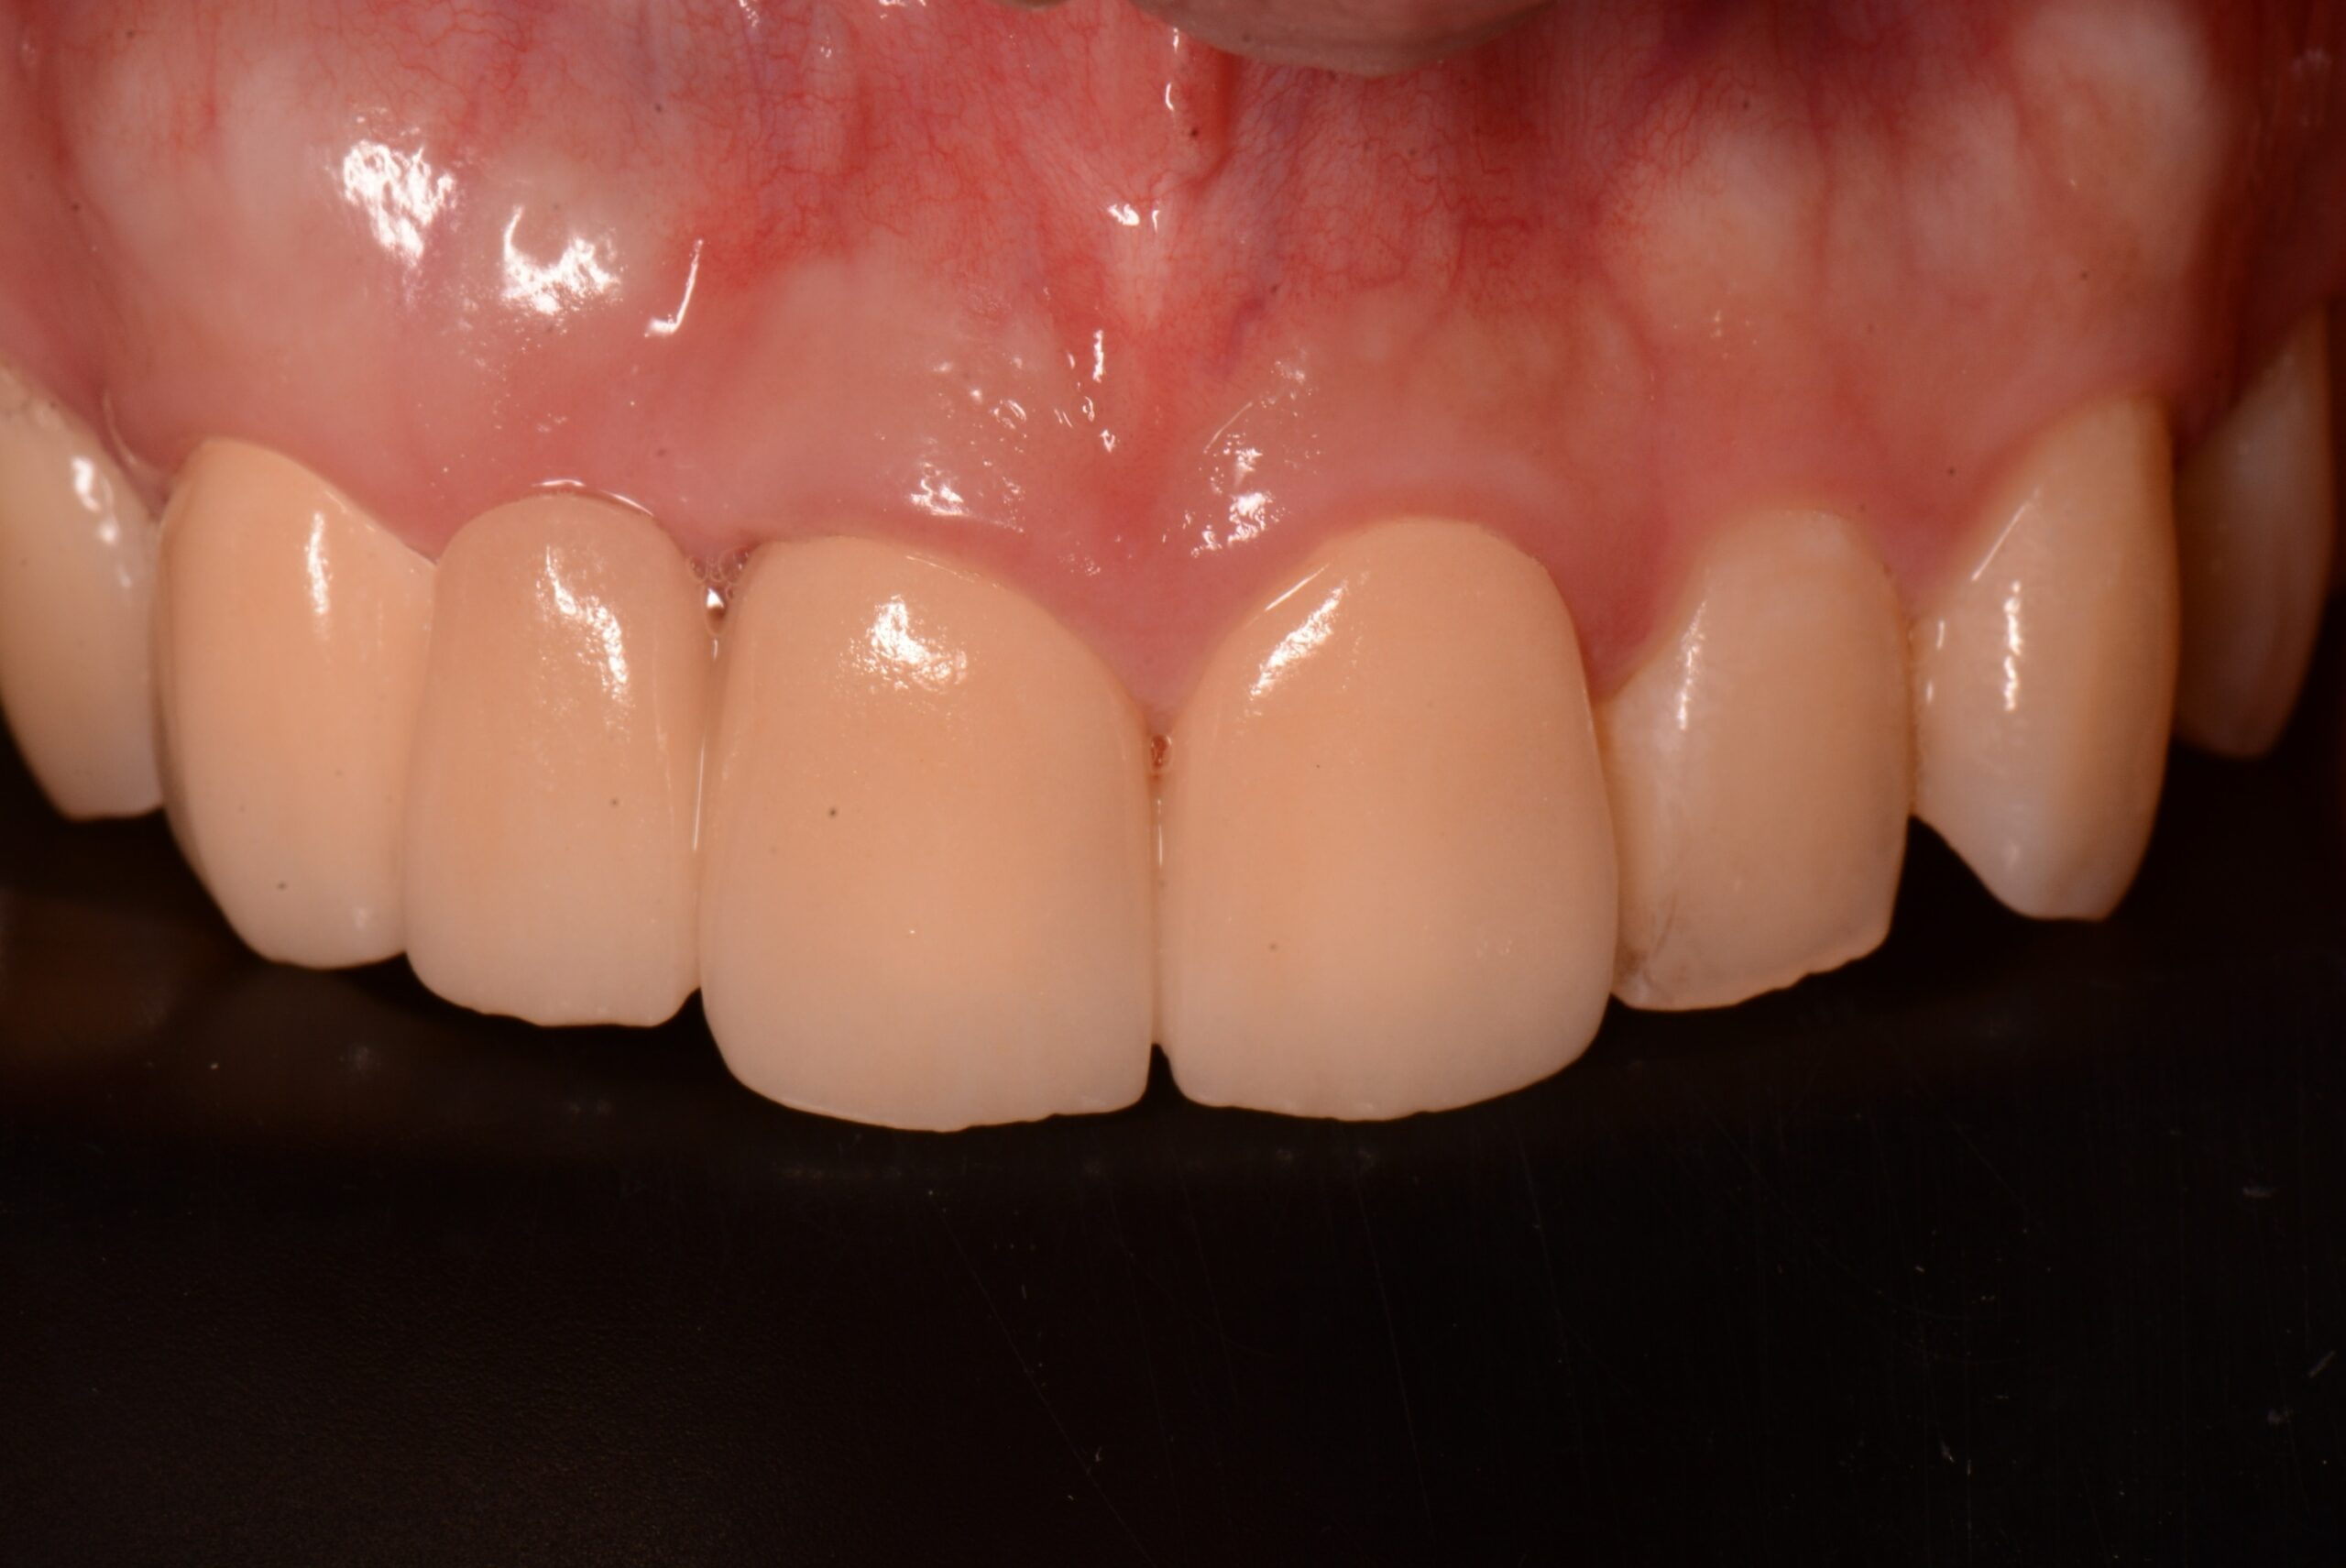

補綴(セラミック)

Before

After

年齢

22歳

主訴

外傷で前歯が抜けた

治療期間

約3ヶ月

治療費

約450,000円

概要

外傷により前歯を失い、「見た目が気になる」「前歯で噛むことができない」といった機能面・審美面のお悩みを抱え来院されました。診査・診断の結果、自然な見た目と噛む機能を回復させるため、セラミッククラウンによる補綴治療をご提案しました。セラミッククラウンは、天然歯に近い透明感や色味を再現でき、長期的な安定性が期待できる治療方法です。形態・色調は患者様と相談しながら丁寧に調整し、周囲の歯と違和感なく馴染むよう仕上げました。

リスク